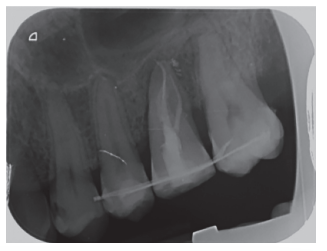

Transcurridos 2 meses se realizó una nueva revisión clínica (Figura 17) y radiográfica mediante radiografía periapical (Figura 18), procediéndose a retirar la ferulización. A los 3 meses se realizó otra revisión clínica (Figura 19) y radiográfica mediante radiografía periapical paralelizada (Figura 20), donde se puede observar una adecuada formación ósea alrededor del diente trasplantado.